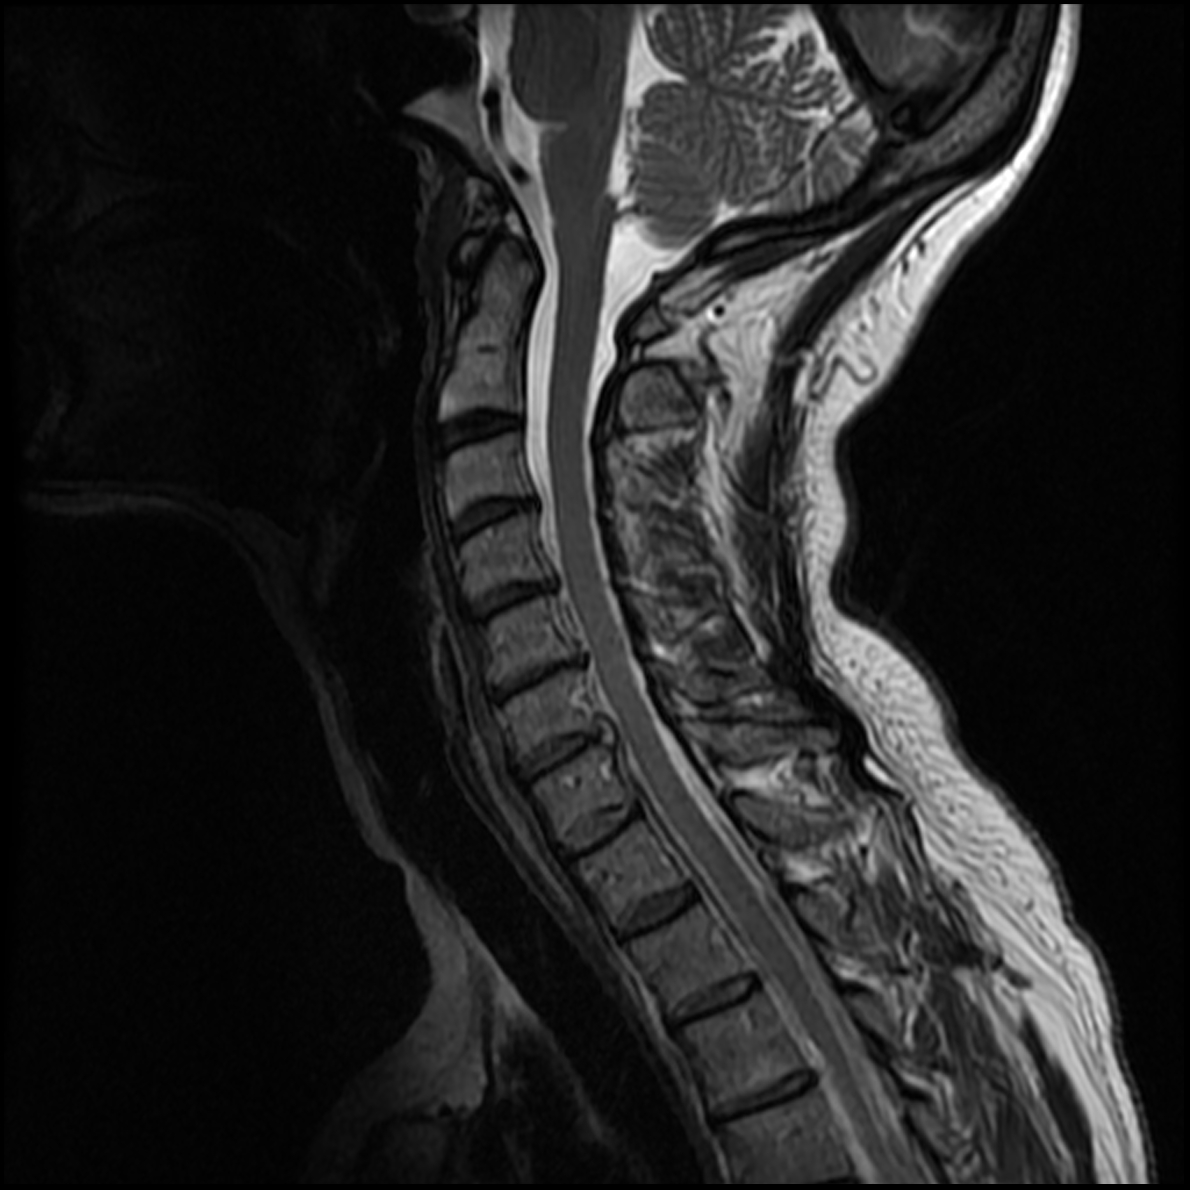

June 2020 MRI

IMPRESSION

- Healed femoral-sided ACL tear with partial attenuation of the proximal ACL fibers.

- Progressive healing of horizontal oblique tear of the medial meniscus posterior horn.

- Chronic inferiorly displaced meniscal flap tear at the lateral meniscus posterior

horn-root junction, less conspicuous than on prior MR imaging. Resolution of previously

noted horizontal longitudinal tear of the body-posterior horn segments. - No new evidence of internal derangement. No acute osseous abnormality.